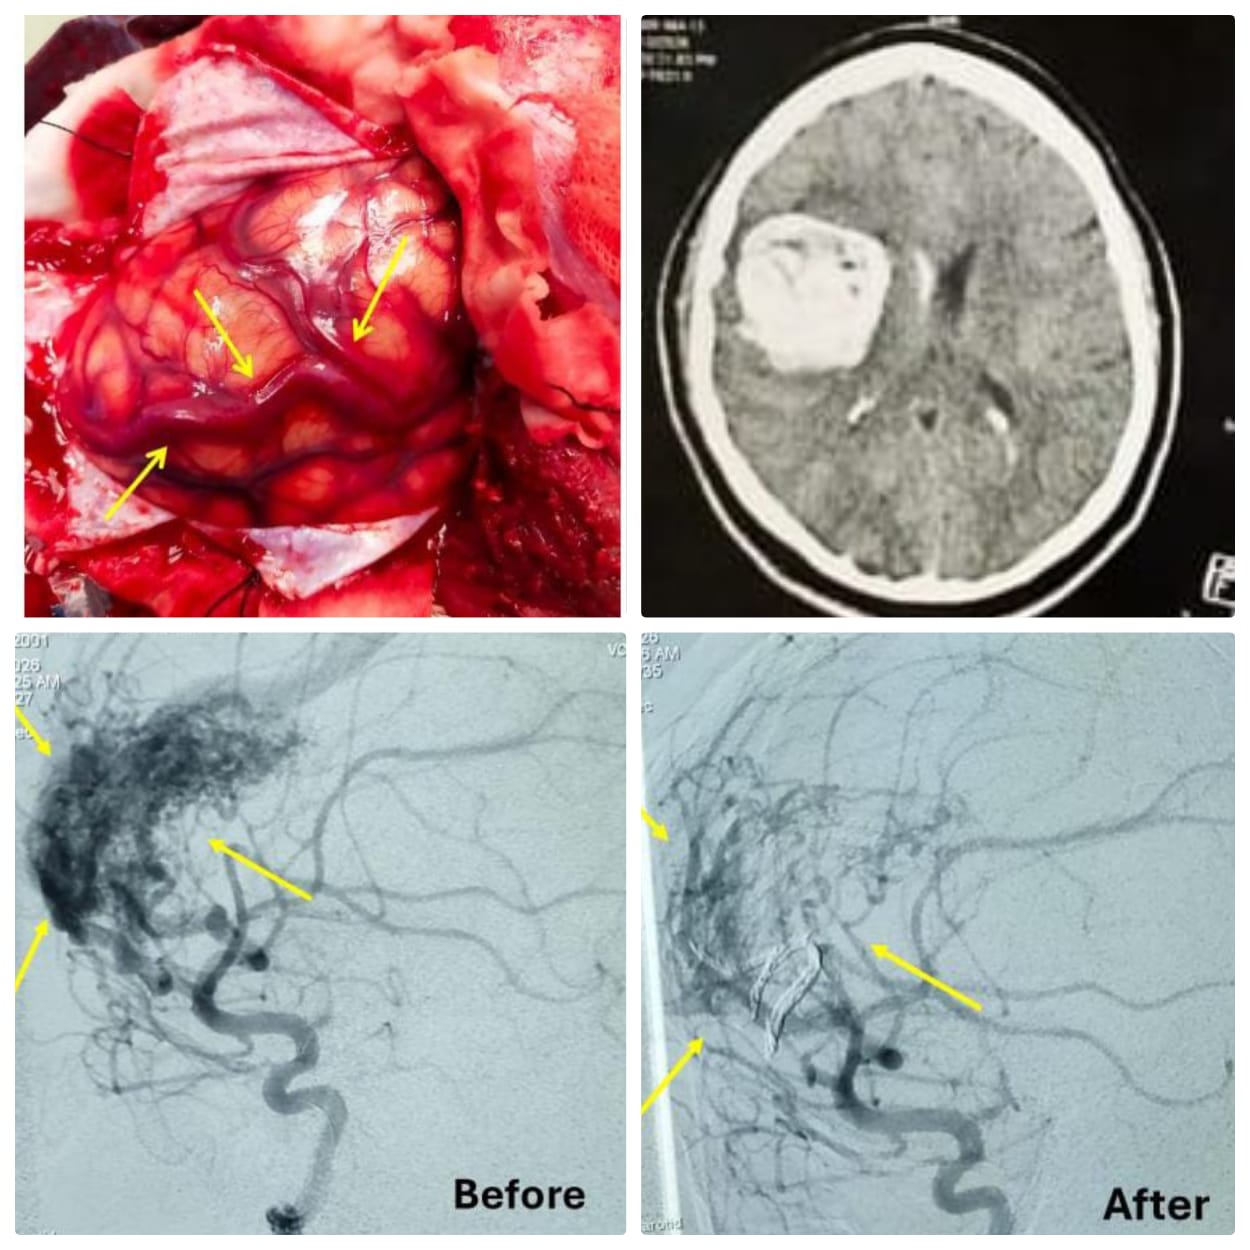

​كان مستشفى صحة المرأة برئاسة الدكتور أحمد إبراهيم، قد استقبل شابة تبلغ من العمر 26 عاما،  تعاني من اضطراب حاد في درجة الوعي ودخولها في غيبوبة شبه تامة، ليتم على الفور إجراء الفحوصات اللازمة وأشعة مقطعية أظهرت وجود نزيف حاد بأنسجة المخ، مما استدعى تشكيل فريق طبي مشترك يضم أقسام (النساء والتوليد، جراحة المخ والأعصاب، وطب الأطفال، والتخدير، والعناية المركزة).

​بالتزامن مع ذلك، قام فريق طبي من قسم جراحة المخ والأعصاب، جاء تحت إشراف الأستاذ الدكتور محمد السيد، رئيس القسم، وضم، الدكتور عبدالله رجب الخضري، مدرس واستشاري بالقسم، والطبيب إبراهيم أحمد يوسف، مدرس مساعد بالقسم، والطبيب إسلام مصطفى، طبيب مقيم بالقسم، والأستاذ أحمد محمد، تمريض بقسم جراحة المخ والأعصاب، بإجراء عملية جراحية دقيقة لتوسيع الحجرة المخية للسيطرة على ارتشاح المخ، حيث تبين وجود نزيف ناتج عن تشوه شرياني وريدي (AVM).

و​عقب الجراحة، نُقلت المريضة إلى العناية المركزة تحت "غيبوبة صناعية" للحفاظ على استقرار علاماتها الحيوية، حتى تم التنسيق مع فريق طبي #بقسم_الأشعة_التشخيصية بالمستشفى الرئيسي، جاء تحت إشراف الأستاذ الدكتور خالد عبد العزيز، مدير المستشفى الرئيسي، والأستاذ الدكتور حسن مجلي، رئيس قسم الأشعة التشخيصية والتدخلية، وضم كل من الأستاذ الدكتور مصطفى هاشم، أستاذ الأشعة التدخلية، والدكتور محمود رفعت، والدكتور محمد عبد الوهاب، مدرسين بالقسم.

وفي غضون أقل من 24 ساعة، أجرى الفريق الطبي قسطرة مخية تشخيصية وعلاجية، تم خلالها غلق التشوه الشرياني باستخدام تقنية (Onyx embolization) بنجاح تام.